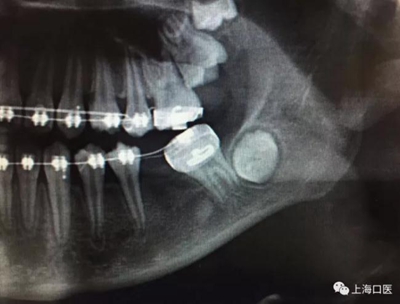

這是上海武廣增正畸工作室接診的一例非常規(guī)拔牙矯治病例,患者女性,初診年齡14歲。LL6殘冠拔除。LL7近中平移取代LL6,我們上傳了該患者一組下頜磨牙近中平移連續(xù)矯治過程的正畸X線片,與正畸界朋友分享。

來源:武廣增 上海口醫(yī)